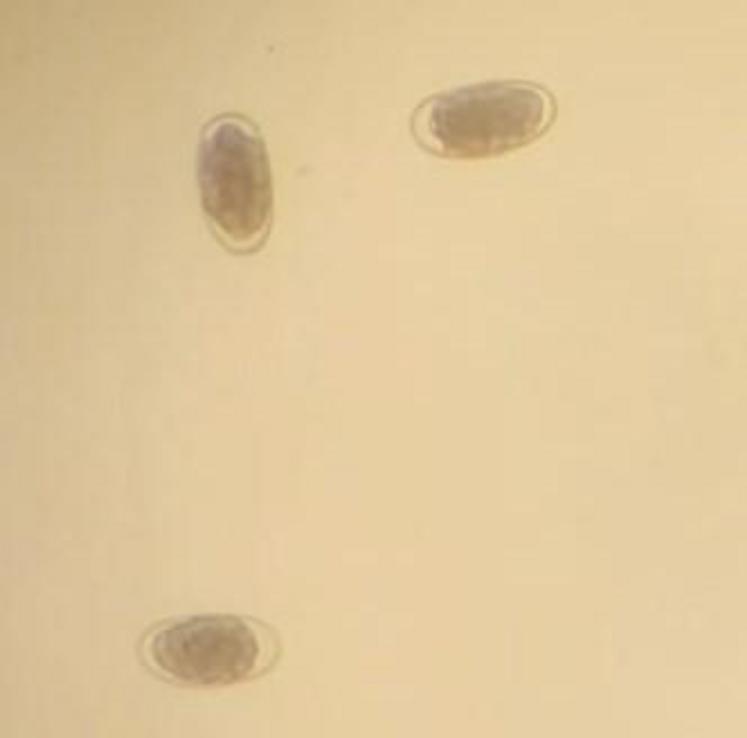

Strongle digestif au microscope chez une brebis présentant un affaiblissement (analyse faite le 6/09/23).

À titre d’exemple, on peut dénombrer le nombre de parasites excrétés dans les selles. Quand la limite de traitement est généralement admise à 500 œufs par gramme (opg), certains vétérinaires relatent couramment des valeurs de plus de 2 000 opg, voire même plus de 20 000 opg en cas d’autopsie. Pour d’autres parasites qui excrètent très peu, un seul œuf présent conduira au traitement.